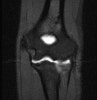

4. MR Arthrography : Useful for evaluation of the collateral ligaments and cartilage surfaces.

5. Elbow Arthrography : UCL pathology in throwers, Osteochondral lesions and repair, Loose bodies